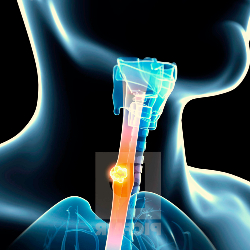

THROAT

Tonsillectomy

Tonsillectomy is a surgical procedure in which both palatine tonsils are fully removed from the back of the throat.